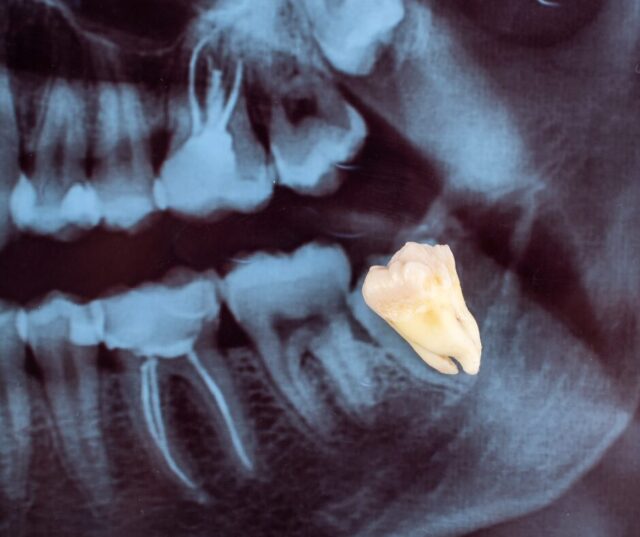

Pantomogram przed usuwaniem ósemek - RTG zębów w Pro Endodentica Łódź Bezpieczna ekstrakcja zaczyna się od planu. Standardem jest zdjęcie punktowe lub pantomogram, a przy dolnych zatrzymanych ósemkach bardzo często wykonujemy CBCT (tomografię stożkową). Dzięki temu:

• dokładnie oceniamy kształt i liczbę korzeni oraz ich bliskość do kanału żuchwowego i zatoki szczękowej,

• przewidujemy trudności i dobieramy technikę minimalizującą uraz tkanek,

• skracamy czas zabiegu i ograniczamy ryzyko powikłań.